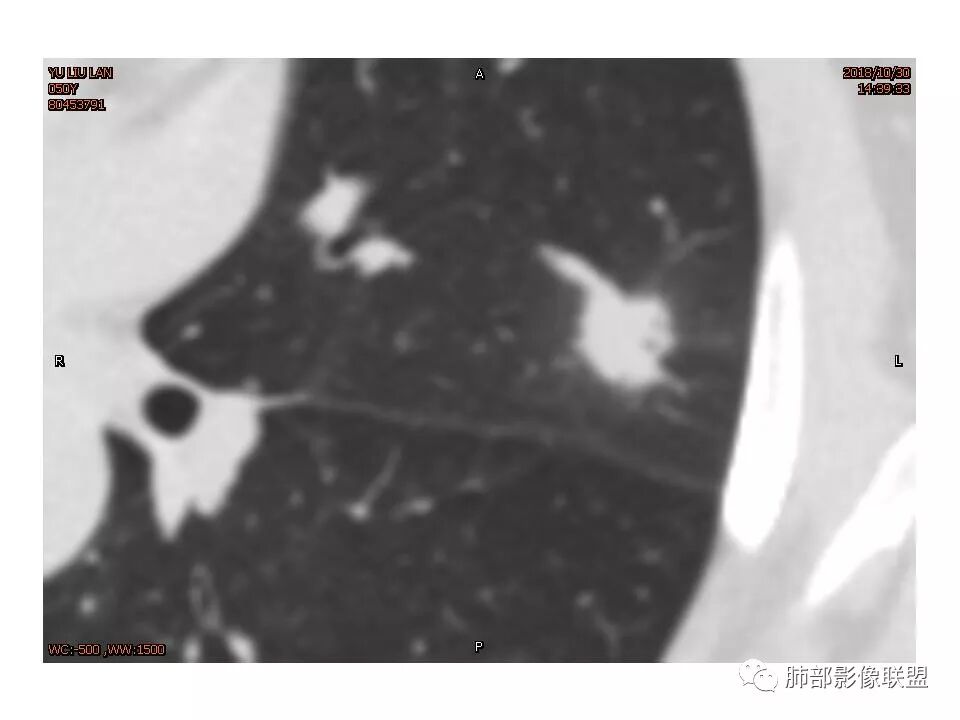

左肺上叶结节影,边缘清晰(周围似见磨玻璃影,需薄层观察),分叶,粗毛刺,月牙铲,血管穿行,胸膜脐凹征,增强不均匀强化,考虑腺癌,病灶部分边缘平直,磨玻璃缘模糊,先抗炎治疗后复查

炎性征象多,平直,长毛刺,尖角征,周围晕模糊,炎性病变放前,腺癌待删,抗炎后复查

结节样病灶,u型征,病灶内可见细支气管管,增强可见血管进入,略增粗,病灶周围有晕,有软毛刺,局部叶间胸膜有牵拉,考虑良性炎性病灶,抗炎后复查。

左肺上叶结节样高密度,边缘稍模糊、平直,见长毛刺,周围血管增粗,患者体检发现,考虑隐球菌,鉴别腺癌(老年女性,似见有分叶),

左上肺结节 周围磨玻璃边缘模糊 结节周围有短及长毛刺 虽有收缩力 但病变边缘收缩较多 长毛刺对邻近外侧胸膜没什么收缩 增强有延迟强化 进入血管稍增粗 首先考虑炎性 感觉炎症吸收过程中也可以这样 腺癌待排

平直征、U型征、长毛刺

细小毛刺,梳状平行,周围边缘模糊晕,血管未收侵犯,支气管未见牵拉扩张,多条淋巴道与胸膜相联,倾向于炎性病变

左上肺实性结节,有血管集束、分叶、棘突、胸膜牵拉、长毛刺为主,周围有晕边界不清,有恶性征象但还是感觉炎性(PC?)可能大

女性,50岁。U型凹陷、平直征

南边:支持炎性

长毛刺比较软。旁边是卫星灶吗?

1.胸膜下略不规则实性密度结节影,孤立,缺乏典型深分叶,可见淡薄边界模糊磨玻璃晕,可见相对细长软毛刺。

2.如南边老师分析,病灶缺乏边缘膨隆优势,甚至部分平直内收。

3.病灶收缩力不强,整体强化程度不显著。

4.综上,病灶更符合炎性,如隐球菌感染等,而不大符合肺腺癌。具体到机化性肺炎略有些出乎预料。